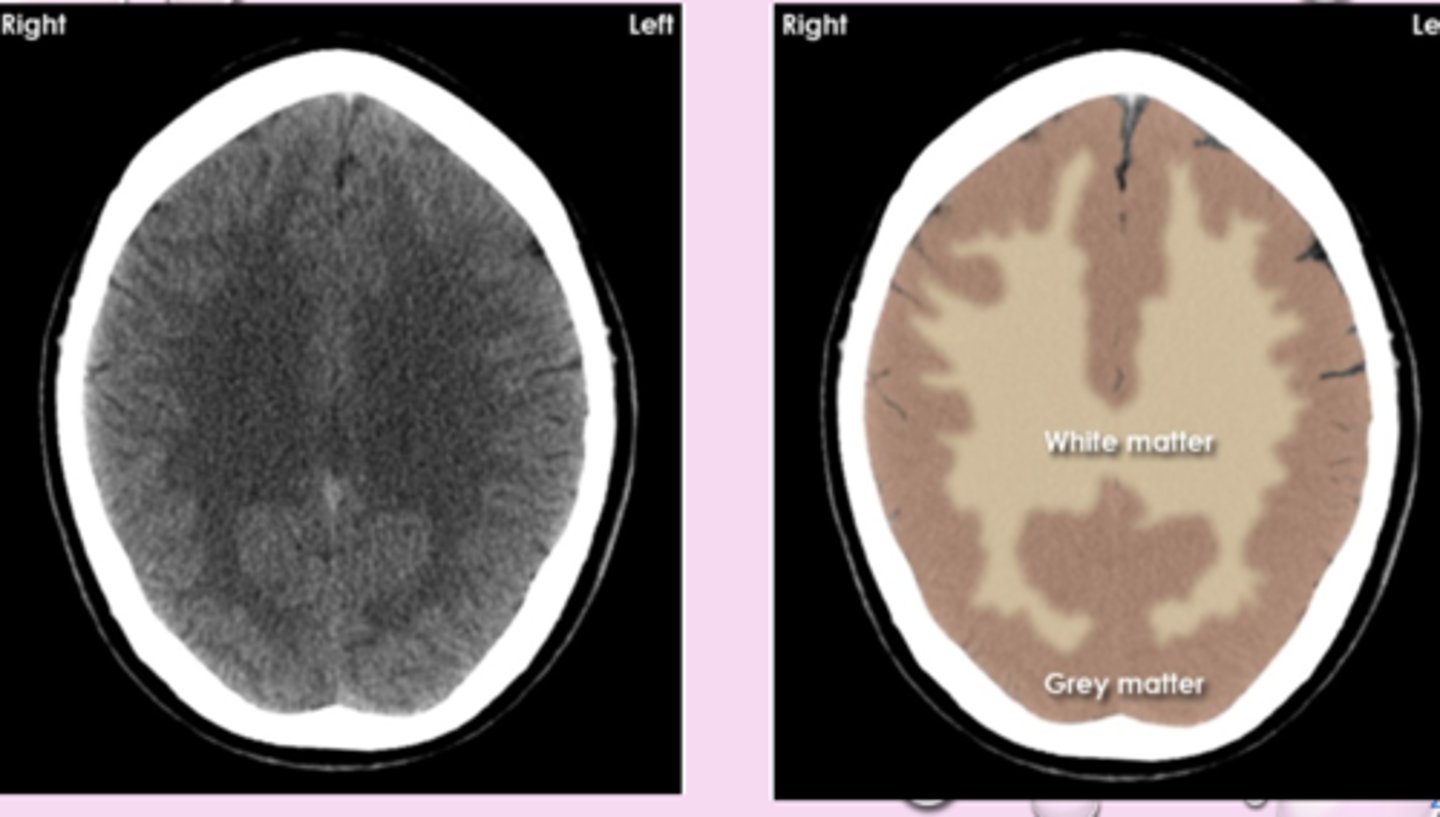

CT interpretation

denser tissue is brighter (hyperdense)

less dense is darker (hypodense)

bone is white, air is black

brain window- structures to be identified and differentiated

white matter appears

blacker than grey matter because it has high content of myelinated axons and lower density

cytotoxic edema

loss of grey-white differentiation

-cant distinguish them from each other